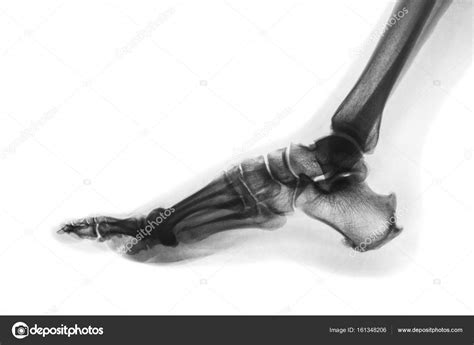

A Lateral Foot X Ray is a type of radiographic imaging that captures a side view of the foot. This view is essential for evaluating the alignment and integrity of the bones, joints, and soft tissues in the foot. Unlike an anteroposterior (AP) view, which provides a front-to-back image, a lateral view offers a different perspective that can reveal issues not visible in other projections.

• Bone Alignment: It helps assess the alignment of the foot bones, which is crucial for diagnosing conditions like flatfoot or high arches.

• Fracture Detection: It can detect fractures that may not be visible in other views, especially in the calcaneus (heel bone) and metatarsals.

• Joint Assessment: It provides a clear view of the joints, helping to identify arthritis, dislocations, or other joint-related issues.

• Soft Tissue Evaluation: While primarily used for bone evaluation, it can also show soft tissue abnormalities, such as swelling or foreign bodies.

Interpreting a Lateral Foot X Ray

Interpreting a lateral foot X ray requires a trained eye and knowledge of foot anatomy. Here are some key points to consider:

• Bone Density: Assess the density and clarity of the bones. Abnormalities in bone density can indicate conditions like osteoporosis or bone tumors.

• Bone Alignment: Check the alignment of the bones, particularly the calcaneus, talus, and metatarsals. Misalignment can indicate fractures, dislocations, or deformities.